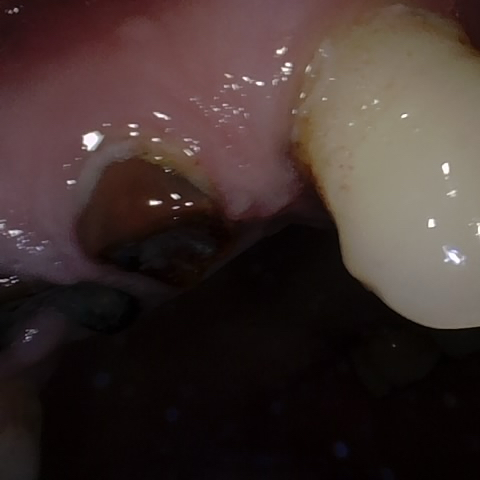

Annotated as "Good"